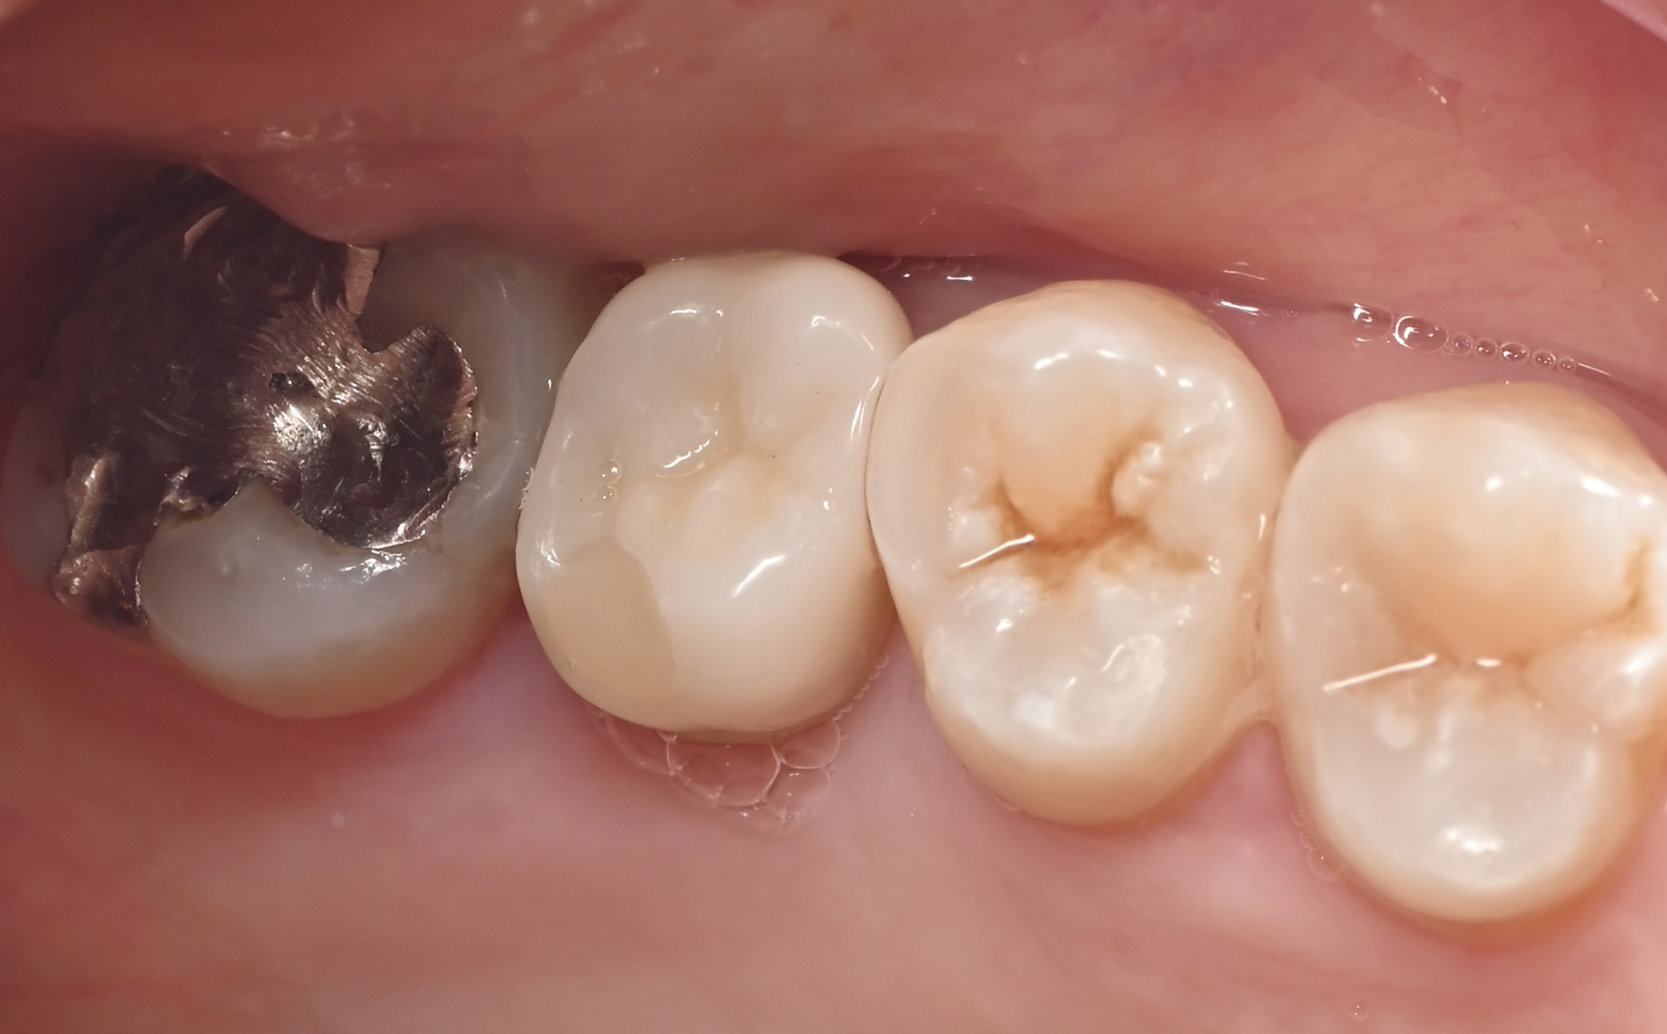

インプラント症例5

治療前

治療後

| 年齢・性別 | 60代 男性 |

|---|---|

| 主訴 | 右上6が他院にてインプラントできないと言われたため 当院にてインプラン ト治療を希望 |

| 治療内容 | 右上6を抜歯し、3か月後にインプラント埋入を行った。 上顎洞底まで骨量が 不足していたため、ソケットリフトを同時に行った。埋入後3か月後に上部構 造(ジルコニア)を装着した。 |

| 治療期間 | 6ヶ月・10回 |

| 治療費用 | 総額:495,000円(税込) 【内容】 インプラント埋入手術 270,000円 ソケットリフト 50,000円 インプラント被せ物 130,000円 |

| リスク・副作用 | ・外科処置が必要 ・自費診療(保険適用外)となる ・ソケットリフト後、稀に上顎洞内感染の可能性がある |